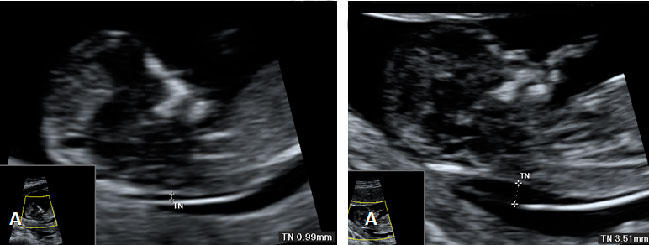

Ecografía Embarazo 4D Semana 12 - PLIEGUE NUCAL